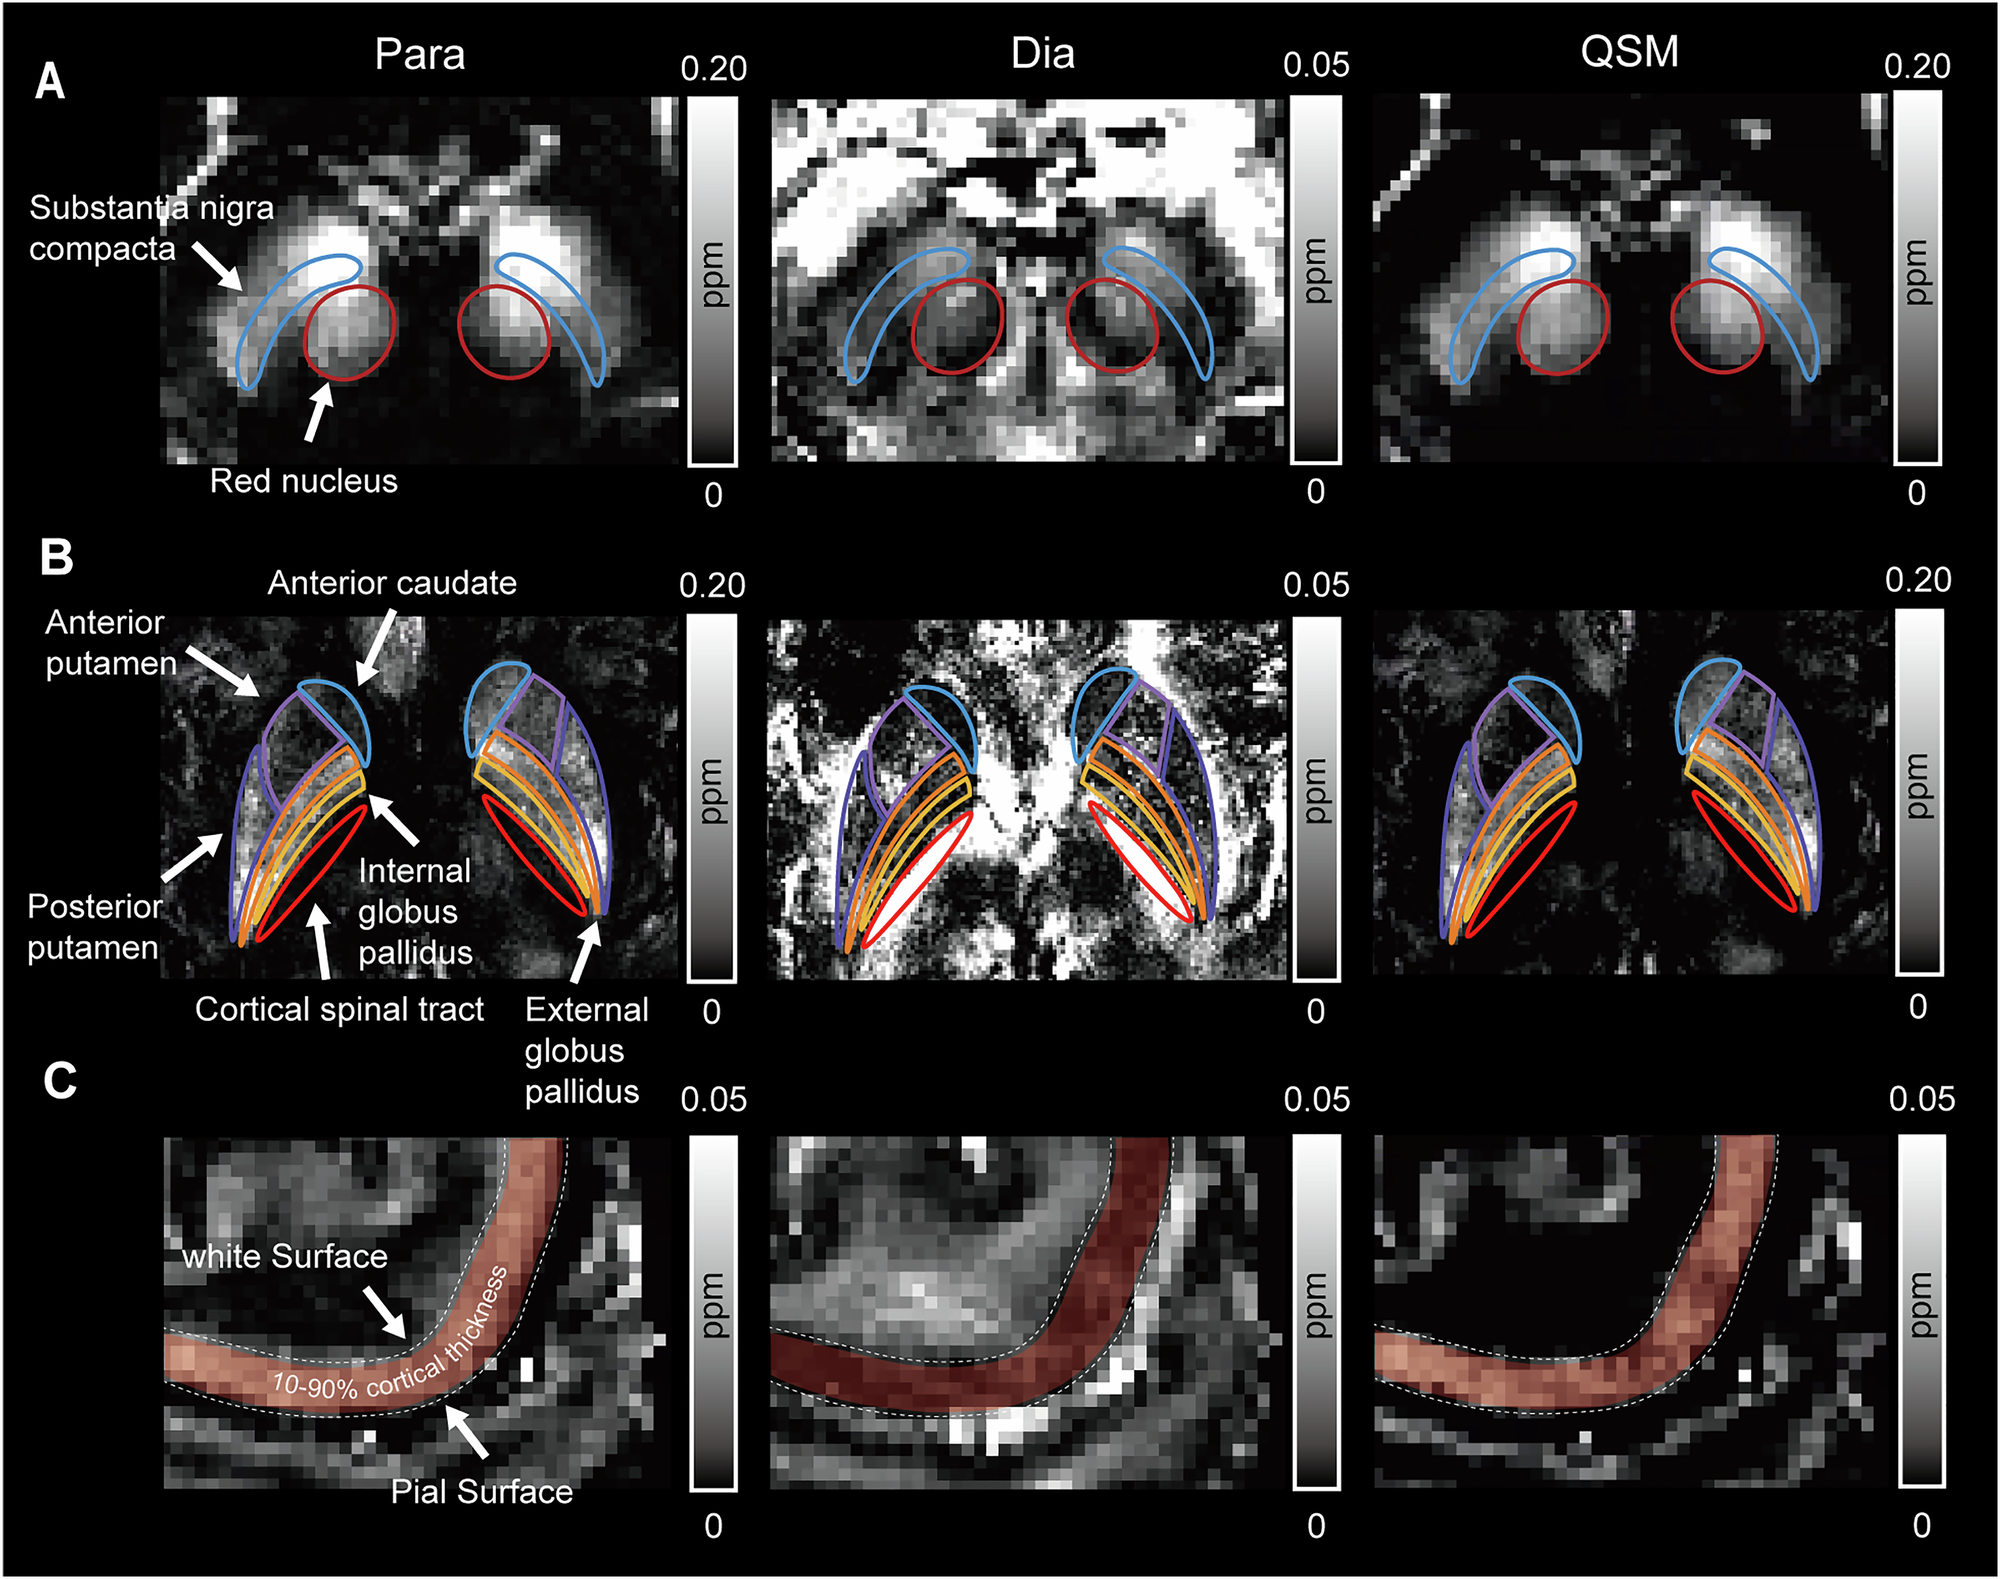

Fig. 5: Regions of interest shown in paramagnetic, diamagnetic, and quantitative susceptibility images.

The ROIs included A substantia nigra pars compacta and red nucleus, B anterior putamen, posterior putamen, anterior caudate, internal and external globus pallidus, and cortical spinal tract, C precentral gyrus. Para paramagnetic susceptibility mapping, Dia diamagnetic susceptibility mapping, QSM quantitative susceptibility mapping, ppm parts per million.